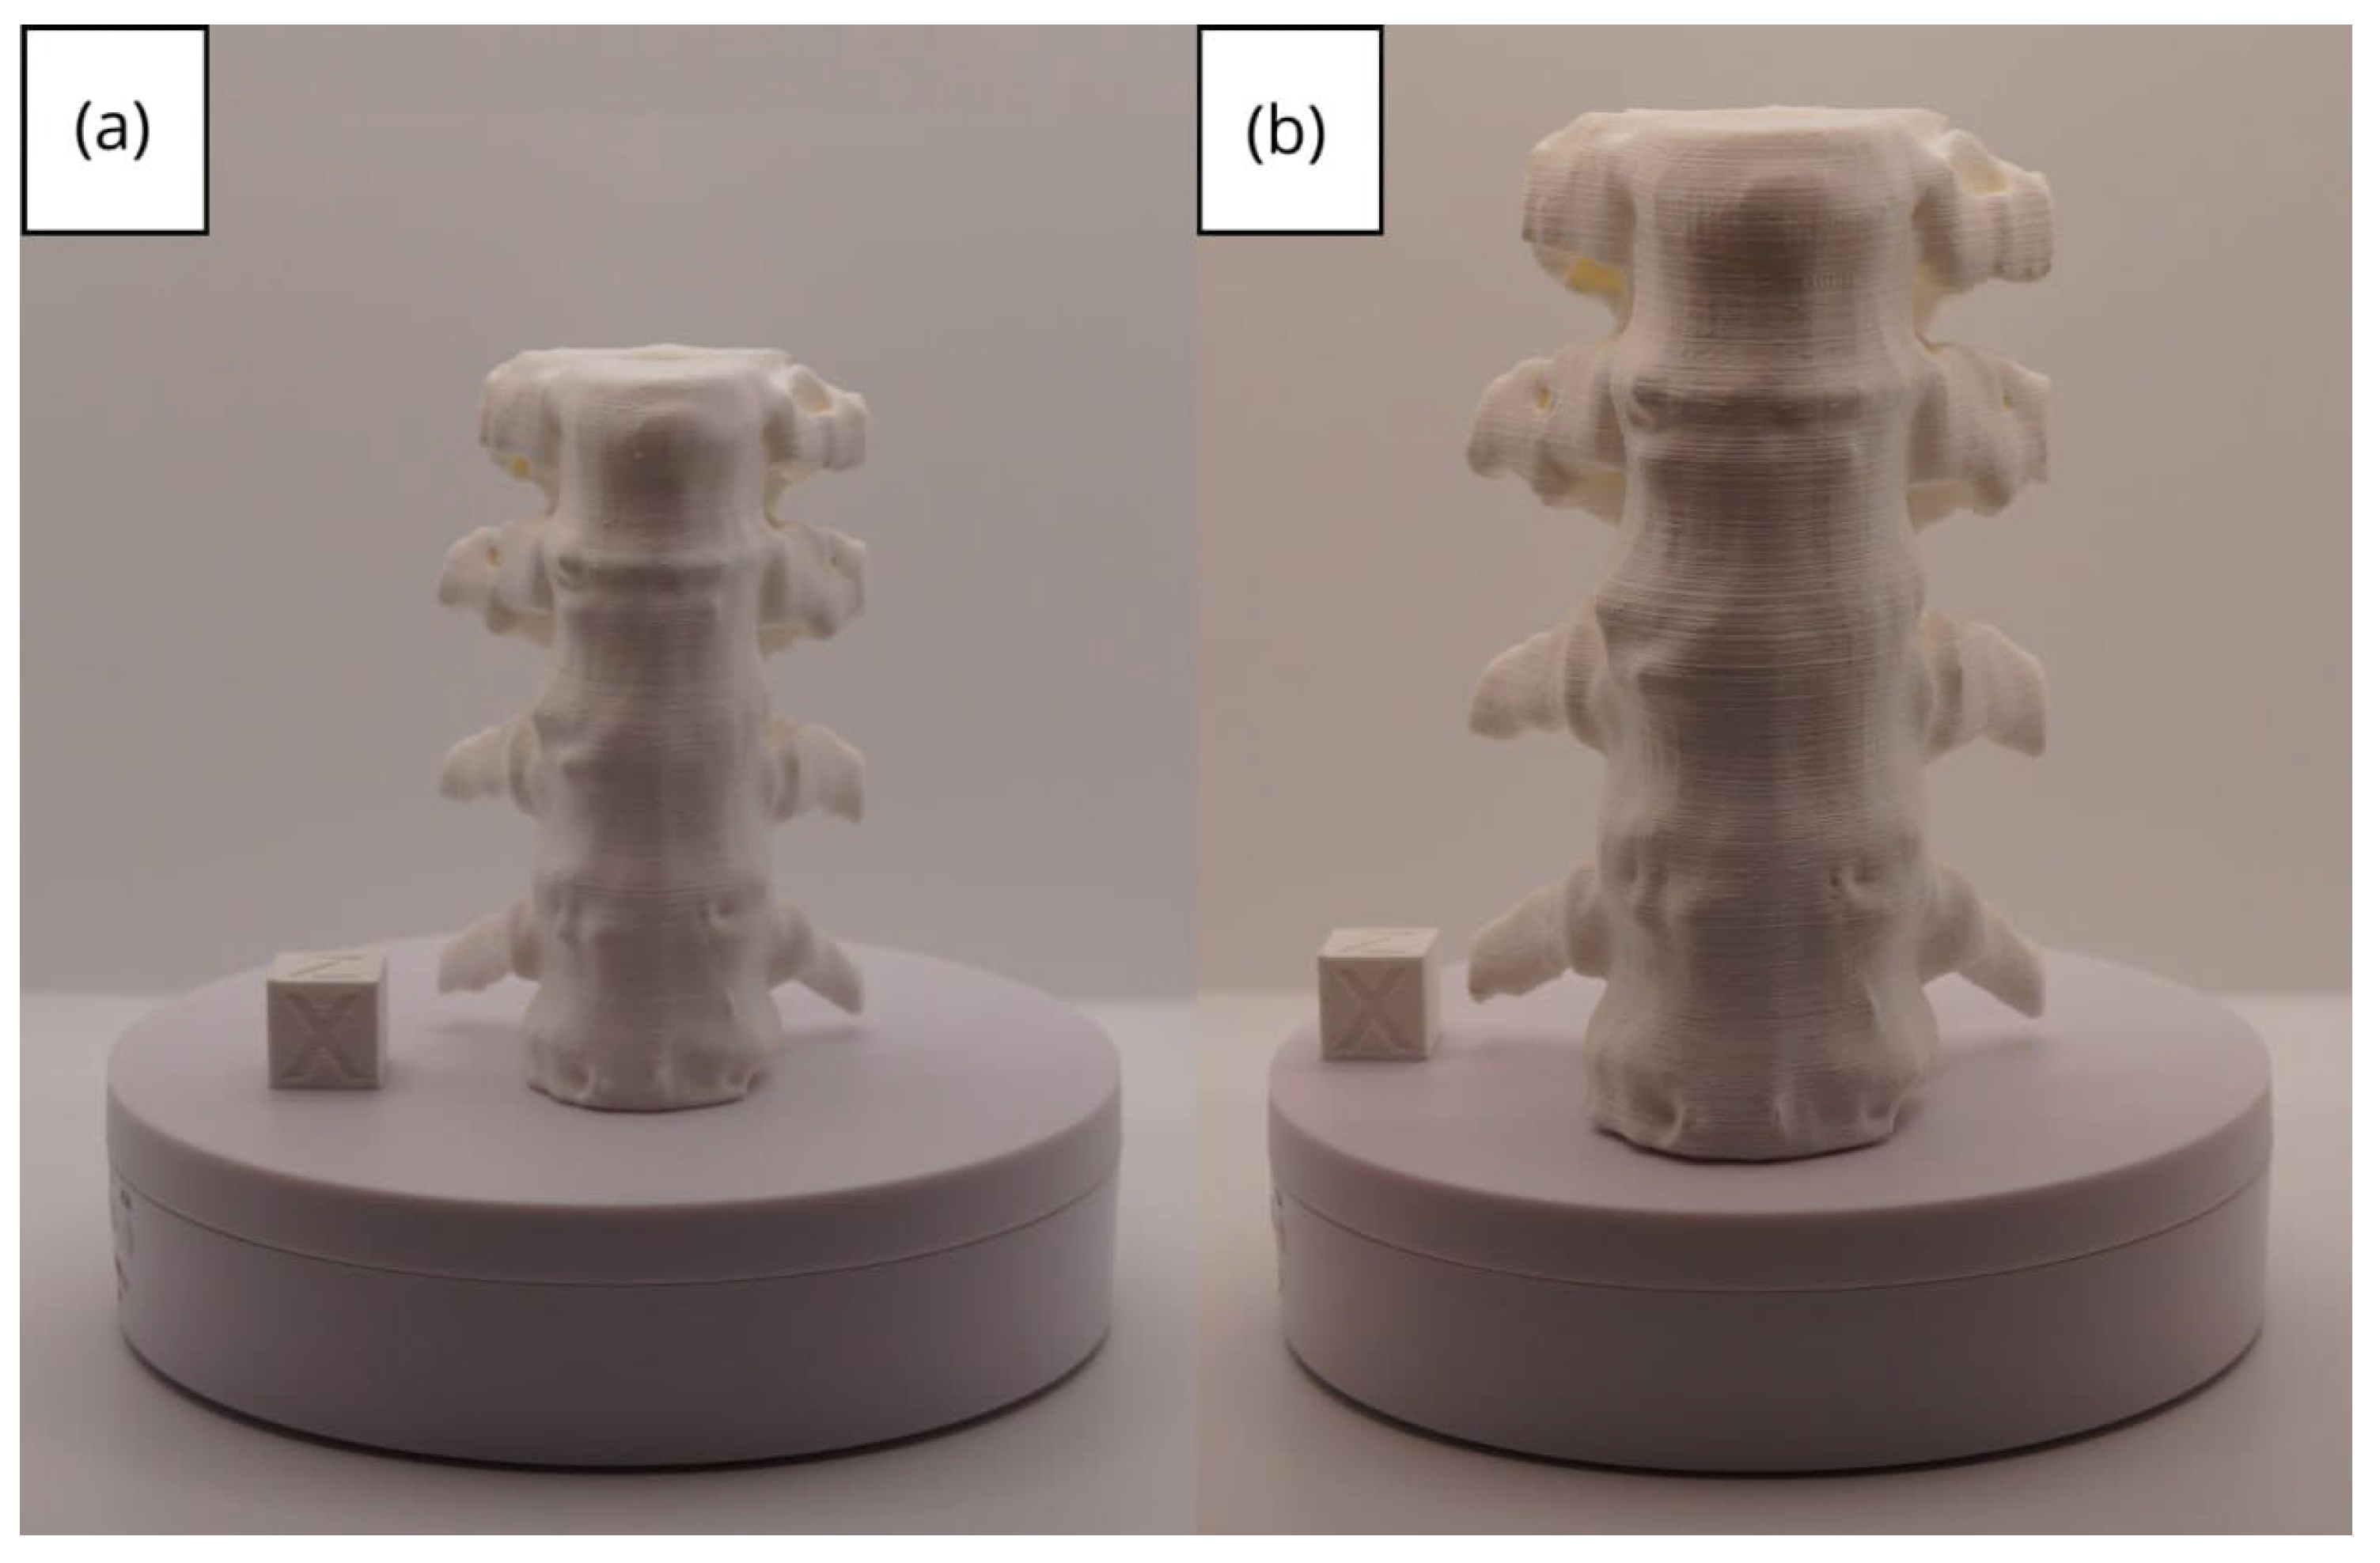

3.1. A Simple and Common Case

3.1.1. DICOM-to-STL File

3.1.2. STL-to-GCODE File

3.1.3. Final Printing

| Vertebrae | [150, 300] | Median | 0.8 | 0.18 | 25 |

| Vertebrae models | m; m | Artillery Sidewinder X2 |

| m; m | Creality Ender 3 | |